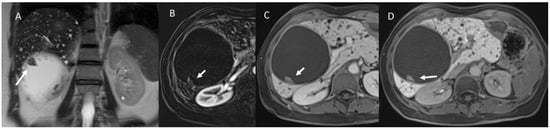

4. Fibropolycystic Liver Disease

6.5. Diagnostic Management